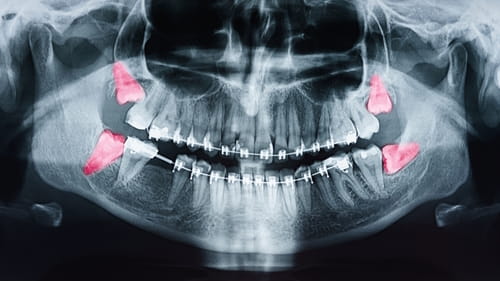

• Extração dos terceiros molares (sisos)

A remoção dos dentes sisos, quando indicada for, deve ser feita preferencialmente entre os 10 e 20 anos, pelo fato da raiz do dente não estar totalmente formada, facilitando assim a sua remoção.

2. A cirurgia de remoção de siso é complicada?

A complexidade do procedimento cirúrgico varia de caso a caso. Com o avanço e desenvolvimento das técnicas, exames pré-operatórios (radiografias) e medicações disponíveis, as cirurgias de remoção de sisos são mais tranquilas.